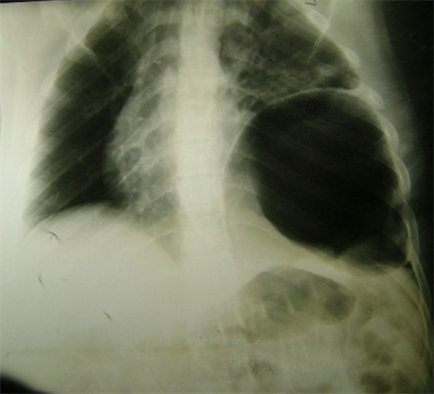

After the first resuscitation measures were made, only 9 patients were able to perform thoracoabdominal scan (33.3%). Standard X-rays (Figure 2) were performed in 18 patients (66.6%) and abdominal ultrasound in 15 patients (55.5%). The diagnosis was made preoperatively in only 13 patients (48.1%).

Figure 2. Chest X-ray showing left diaphragmatic hernia.

However, the diagnosis of TRD remains difficult to make and was made preoperatively in only 48.1% of our patients. It has been reported in a developed setting that, 43.5% of cases of diaphragmatic rupture were diagnosed pre surgically, 41.4% during surgery or autopsy, and 14.6% post surgically [15]. Diagnosis depends on a high index of suspicion, careful examination of the chest x-ray or CT scan in patients with thoracoabdominal or polytrauma, and systematic inspection of the diaphragm when operating for concurrent injuries [15]. According to the literature [16], 92.6% of the TRDs in our series were on the left side. Possible explanations are: the liver buffered external forces applied to the abdomen or flank and delivered to the diaphragm through the intra-abdominal organs, the diaphragm is naturally stronger on the right side than on the left side, and the detection of diaphragmatic rupture on the right side is more difficult than detection on the left side [16].